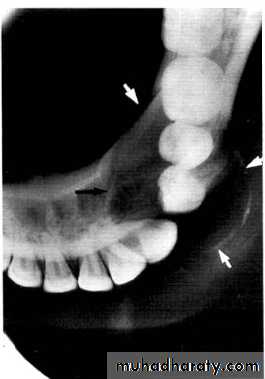

Multilocular appearance, expansion (arrowed) and considerable displacement of the adjacent teeth.

Buccal and lingual expansion (arrowed) and the undulating cortical border.